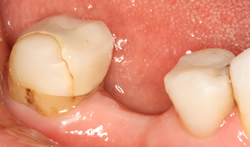

| Before | After |

Cantilever Bridge – This is a bridge with one false tooth or ‘pontic’ which is attached to one crown ‘the abutment’

Fixed- Fixed Bridge – Generally consists of three crowns joined together, one at each end which cover your natural teeth and a crown in the middle which replaces your missing tooth.- Some bridges may actually be four, five or even more crowns joined together, designed to replace more than one of your missing teeth

Adhesive Bridge – This bridge has a false tooth (the pontic) to which a metal or tooth coloured ‘wing’ is attached to a natural tooth on either side of the missing tooth. This type of bridge can have one or two wings